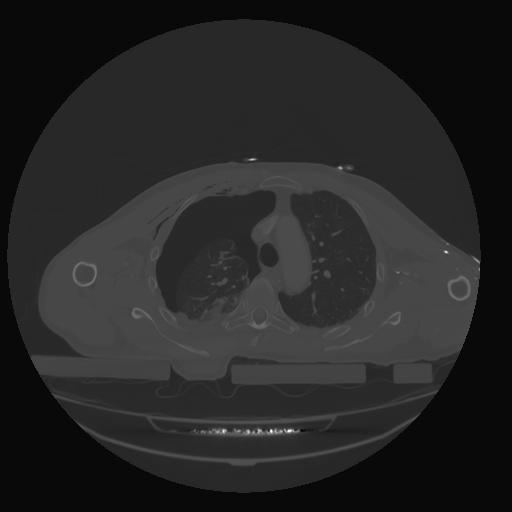

28 CUERPO,CE,Vol,2.0,CUERPO,,